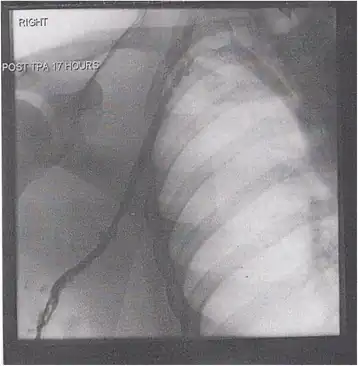

A venogram before catheter-directed thrombolysis for Paget–Schroetter syndrome, a rare and severe arm DVT shown here in a judo practitioner, with highly restricted blood flow shown in the vein -

After treatment with catheter-directed thrombolysis, blood flow in the axillary and subclavian vein was significantly improved. Afterwards, a first rib resection allowed decompression. This reduces the risk of recurrent DVT and other sequelae from thoracic outlet compression.[147]